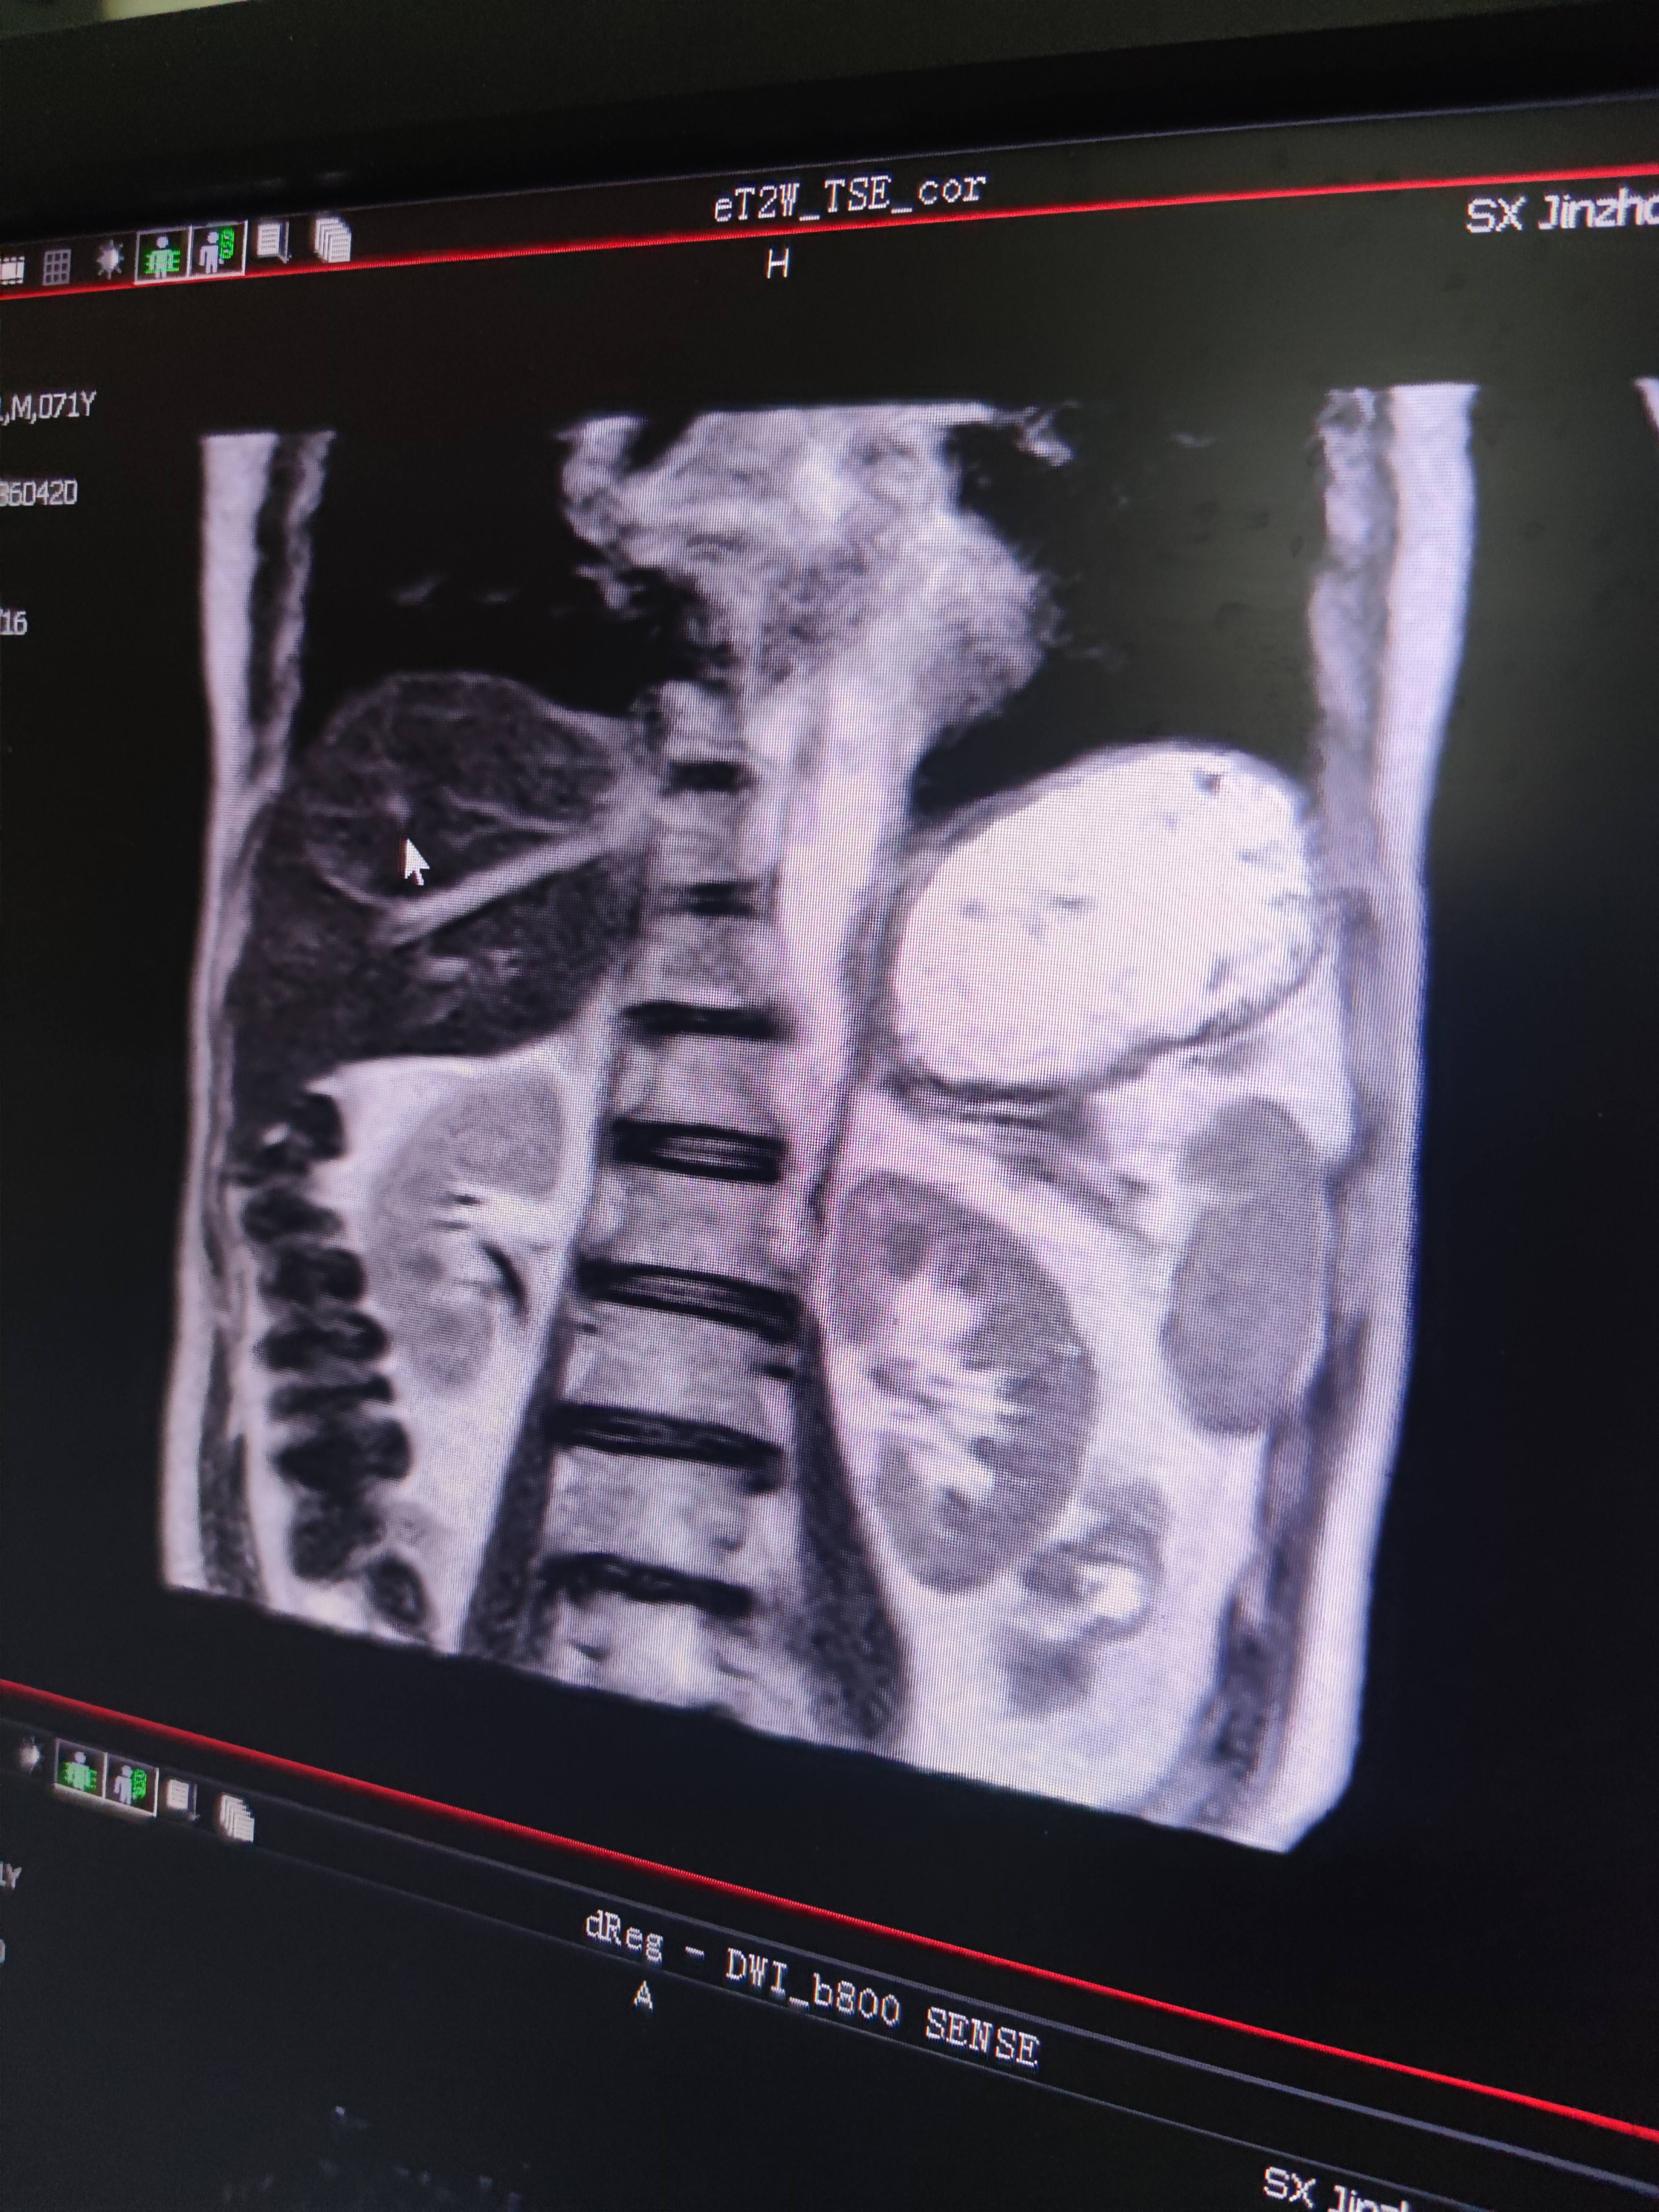

四月份癌胚抗原还是5.6,这个月到8了,持续升高。做了核磁增强,左侧桥小脑角哪有个地方不确定。肝脏核磁平扫弥散有两个点状高信号,转移也排不了,胃肠镜正常,左颈部有个变圆的淋巴结,保险点是不该加个化疗药了?咨询了陈波主任,等结果的吧!图片